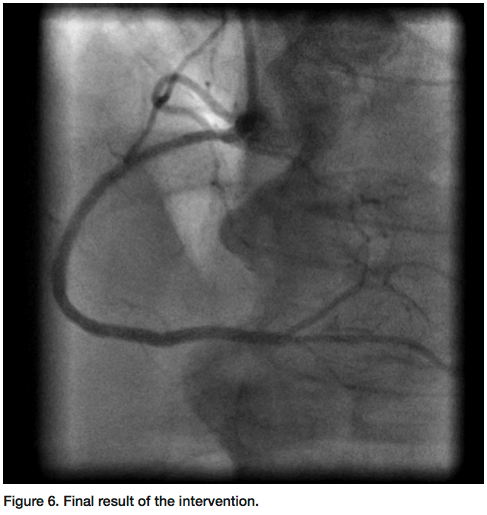

Corporation) was used. The laser softened the cap and allowed us to cross through the entire segment of the CTO with a Kinetix wire. Further lasing was performed at 80 Hertz pulse fluency and at 80 mJ/mm2 repetition cycle for debulking of the entire in-stent occlusion area (Figure 4). A 2.75mm balloon was utilized to pre-dilate the whole length of the CTO. Intravascular ultrasound (IVUS) was performed. Multiple overlapping Ion drug-eluting stents (Boston Scientific) were deployed to the RCA (Figure 5) and post dilated to 3.00 mm, demonstrating excellent angiographic results and TIMI-III flow (Figure 6). The sheath was removed and a hemostatic band was applied for two hours. The patient was discharged the next morning on prasugrel and aspirin along with other medications.